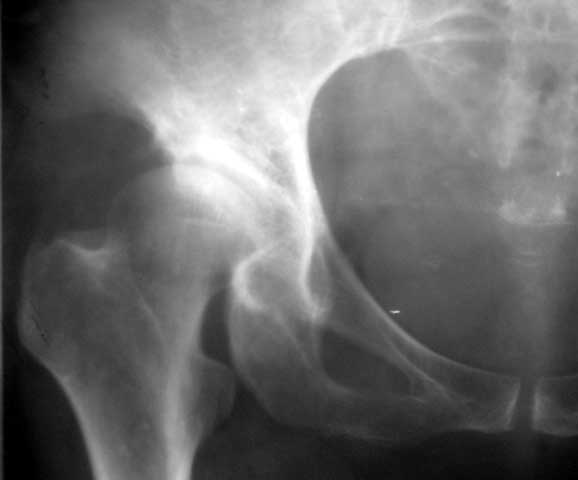

以下是引用yxfjnchina在2005-4-16 19:51:36的发言:[br]双侧髋臼稍浅平,髋臼外上缘可见骨质增生.左股骨头内密度不均,可见小囊状低密度影及不均匀硬化.小梁紊乱.考虑双侧髋臼发育不良并退行性骨关节病.左股骨头缺血性坏死待排

以下是引用dgma在2005-7-1 21:34:00的发言:[br][br]双侧髋臼发育不良。[br]退行性骨关节病。[br]左股骨头缺血性坏死?[br]建议:左股骨头mr扫描。